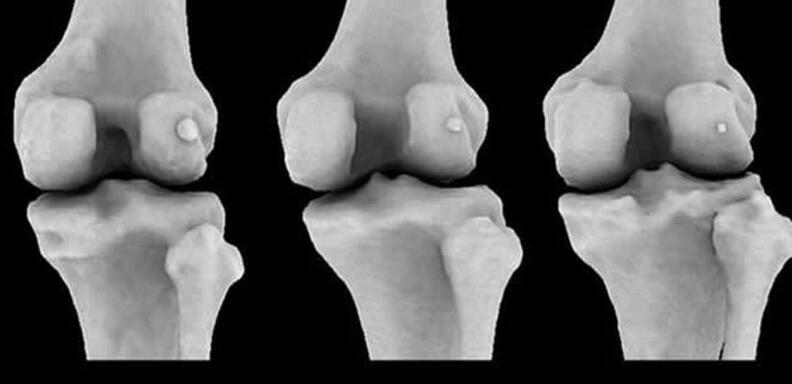

图中显示3个不同膝骨样本存在不同大小的豆骨。科学家发现1918年全球11.2%居民体内存在豆骨,但截至2018年,全球39%居民体内存在豆骨。

英国伦敦帝国理工学院的研究人员回顾了过去150多年进行的2.1万多项科学研究,其中包括研究人员扫描和解剖鉴定发现豆骨的存在。他们从中发现1918年全球11.2%居民体内存在豆骨,但依据发表在《解剖学杂志》的这篇评论报告,截至2018年,全球39%居民体内存在豆骨。

伯托姆博士称,当远古灵长目动物进化成大猿和人类,我们似乎已不再需要豆骨,现在它只会给我们带来麻烦,但有趣的是,近年来人体出现豆骨的概率骤增。这项最新研究发表在《解剖学杂志》上,作者详细研究了25个国家21676个膝盖数据,最早的数据可追溯至1875年。这些膝盖数据来自多种渠道,其中包括:X射线、核磁共振扫描和局部解剖。